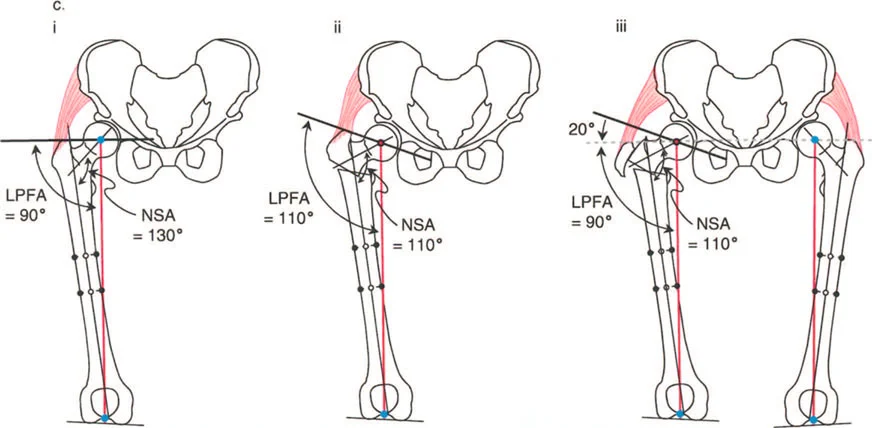

يستخدم جراحو العظام عدة زوايا لقياس محاذاة مفصل الورك وعظم الفخذ، وهي حاسمة في تشخيص التشوهات وتخطيط العلاج:

- الزاوية بين عنق وجسم الفخذ (Neck-Shaft Angle - NSA): هي الزاوية بين محور عنق الفخذ ومحور جسم الفخذ.

- الزاوية الطبيعية: تتراوح عادة بين 125° و 135°.

- كسع الورك (Coxa Vara): تحدث عندما تكون هذه الزاوية أقل من الطبيعي (أقل من 120°)، مما يجعل عنق الفخذ أكثر أفقية.

- فحج الورك (Coxa Valga): تحدث عندما تكون هذه الزاوية أكبر من الطبيعي (أكثر من 140°)، مما يجعل عنق الفخذ أكثر عمودية.

- الزاوية الميكانيكية لعظم الفخذ القريب (Mechanical Proximal Femoral Angle - MPFA): تقيس العلاقة بين محور عظم الفخذ ومستوى المدور الكبير.

- الزاوية الجانبية لعظم الفخذ القريب (Lateral Proximal Femoral Angle - LPFA): تقيس ميل الجزء العلوي من عظم الفخذ.

تؤثر هذه الزوايا بشكل مباشر على ميكانيكا مفصل الورك، وخاصة على ذراع الرافعة للعضلات المبعدة للورك. عندما تكون هذه الزوايا غير طبيعية، يزداد الضغط على المفصل، وتضعف العضلات، مما يؤدي إلى الألم والعرج وتآكل المفصل.

صور توضح حالة كسع الورك مع تضخم المدور الكبير قبل وبعد إجراء قطع عظم واغنر، حيث يتم تصحيح المحاذاة ونقل المدور الكبير.

صور توضح حالة كسع الورك مع تضخم المدور الكبير بسبب مرض بيرثيز، وعلاجها باستخدام قطع عظم مورشر مع التثبيت الداخلي.

- الورك الفاروسي مع المدور الكبير المتضخم: في هذه الحالات، يكون التشوه ناتجًا جزئيًا عن عنق الفخذ وجزئيًا عن تضخم المدور. يتطلب التصحيح الجراحي عادةً قطع عظم فحجي (Valgus Osteotomy) مع نقل للمدور الكبير.

- تشوه فحجي مع دوران داخلي لعظم الفخذ القريب وخلع جزئي للورك: قد يتطلب هذا قطع عظم فاروسي مع إزاحة وسطية ونقل المدور الكبير للأسفل والجانب.

- رأس الفخذ البيضاوي: في بعض حالات كسع الورك، قد يكون رأس الفخذ بيضاوي الشكل. يهدف قطع العظم الفحجي في هذه الحالات إلى جعل المحور الطويل للقطع البيضاوي أكثر أفقية لزيادة مساحة تحمل الوزن وتقليل الضغط على المفصل.